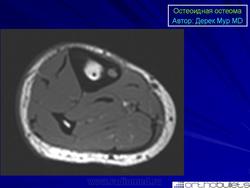

Внутрикорковая остеоид остеома проксимального метафиза большеберцовой кости у 14-летней девочки.

КТ изображение фиксирует периостальную реакцию, утолщение кортикльного слоя, очаг (стрелка) с центральной минерализацией. Имеет место реактивный склероз костного мозга (*), прилегающего к очагу.

МР изображение. «Периостальная реакция» (наконечники стрел).

МРТ позволяет изучить не только сам очаг остеоид остеомы, но и окружающий склероз костной ткани, а также смежные с опухолью участки костного мозга и мягкие ткани.